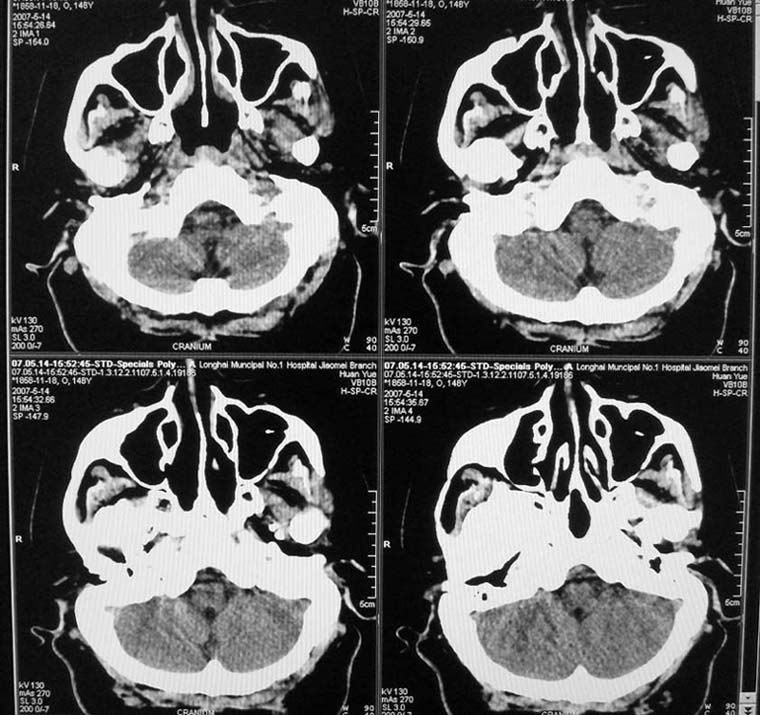

以下是引用天南地北在2007-5-15 23:30:00的发言:[br]看不出来什么[br]建议冠面增强扫描,或mri检查

以下是引用郭凯在2007-5-16 0:17:00的发言:[br]看不到,如果临床支持的话还是做mri看一下吧,对垂体微腺瘤比较敏感.[br]ct上看不到不能乱报.

以下是引用jiangjing在2007-5-16 11:06:00的发言:[br]看不出来什么[br]建议冠面增强扫描,或mri检查